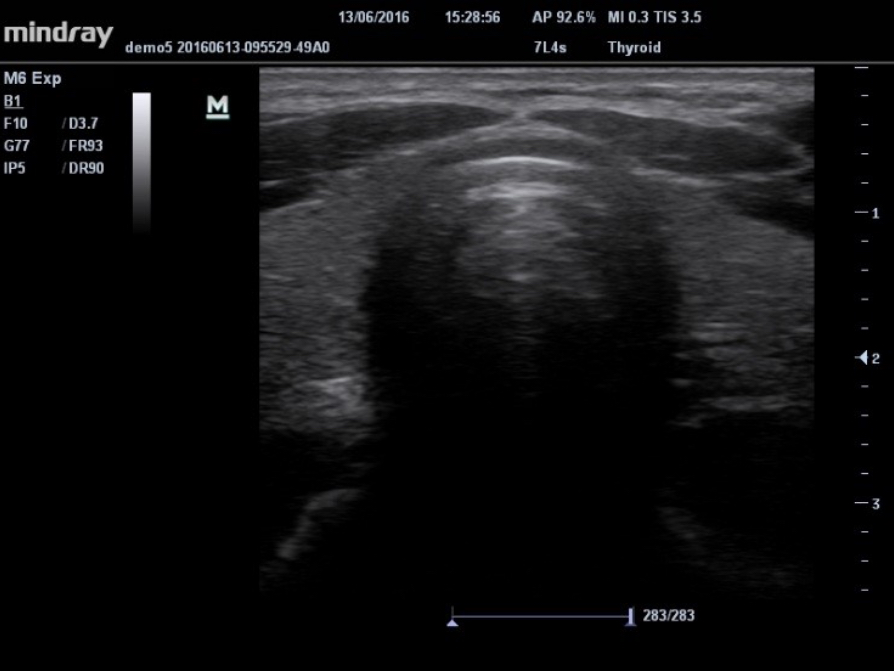

iNeedle?

Su herramienta para realizar una biopsia más profunda: permite ajustar la línea de exploración para obtener una mejor visibilidad de la aguja, los nervios y los vasos peque?os.